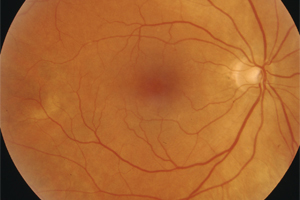

Fundusfotographie

Mit einer Funduskamera, einer speziell für die Netzhautfotografie entwickelte Kamera, werden Veränderungen an der Netzhaut zur Sicherheit fotografisch untersucht und dokumentiert. Wegen der hohen Auflösung und je nach Aufnahmewinkel ermöglicht sie präzise Aufnahmen insbesondere des Sehnerven, der Netzhaut, der Blutgefäße und der Aderhaut. Spezielle Filter liefern dabei Informationen, die bei der einfachen augenärztlichen Untersuchung verborgen bleiben. Der Vergleich von Aufnahmen, die zu unterschiedlichen Zeitpunkten aufgenommen wurden, ermöglicht eine genaue Beobachtung von Krankheitsverläufen. Bei Veränderungen kann somit zeitnah eine entsprechende Therapie oder Therapieanpassung vorgenommen werden.

Was passiert bei der fotografischen Untersuchung?

Bei weitgestellter Pupille (Achtung: keine Fahrtauglichkeit für mindestens 4 Stunden nach der Untersuchung!) werden mit Hilfe eines Auslösers nacheinander mehrere Bilder von der Netzhaut angefertigt. Die Untersuchung ist berührungsfrei und dauert nur wenige Minuten.

Was kann ich von der fotografischen Dokumentation erwarten?

Durch die Farbfotografien können wir sehr viel genauer das aktuelle Stadium der Erkrankung mit den Ergebnissen der vorangegangenen und künftiger Untersuchungen vergleichen. Selbst kleine Veränderungen lassen sich zuverlässig beurteilen. Am Computerbildschirm können wir Ihnen die Befunde im Anschluss an die Untersuchung nachvollziehbar erläutern und – wenn es erforderlich ist – gemeinsam mit Ihnen das weitere therapeutische Vorgehen besprechen.

Darstellung des Augenhintergrundes (Fundus) ohne krankhaften Befund